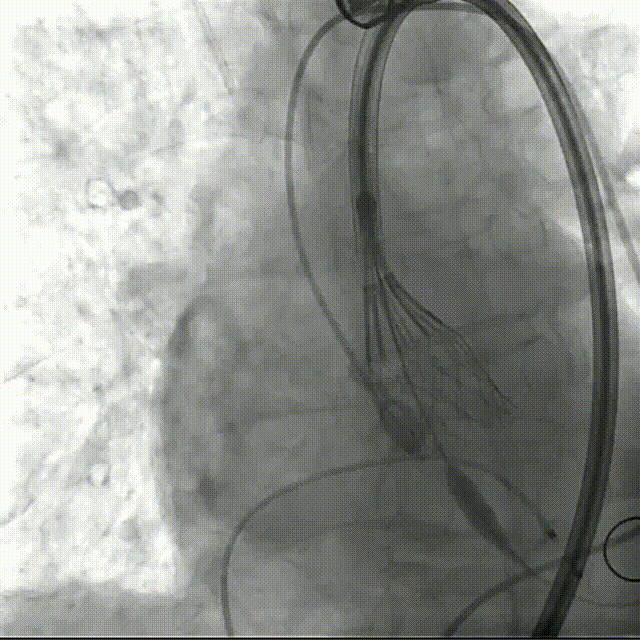

初始造影确定瓣环位置

20mm球囊预扩,无腰有漏;选择27号瓣膜可充分封堵

瓣膜0位定位释放,导丝保持张力,保证同轴性

瓣膜展开后造影评估瓣膜位于0位,无瓣周漏

多角度评估,瓣膜位置可,同轴性佳,可以脱钩释放

脱钩后造影,瓣膜无位移,无瓣周漏